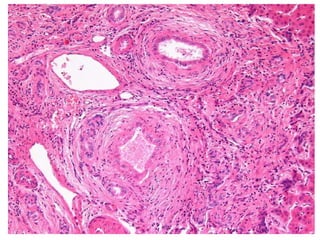

BS09-10453 55 yo, female.  Clinical history:  Elevated ALT/AST. Viral serologies negative.

BS09-10453:  Dx: Chronic hepatitis, with severe activity (bridging necrosis) and portal fibrosis, ? autoimmune hepatitis vs. drug/toxin mediated injury. Corresponds to: Modified Ishak stage 1/4 Metavir F1